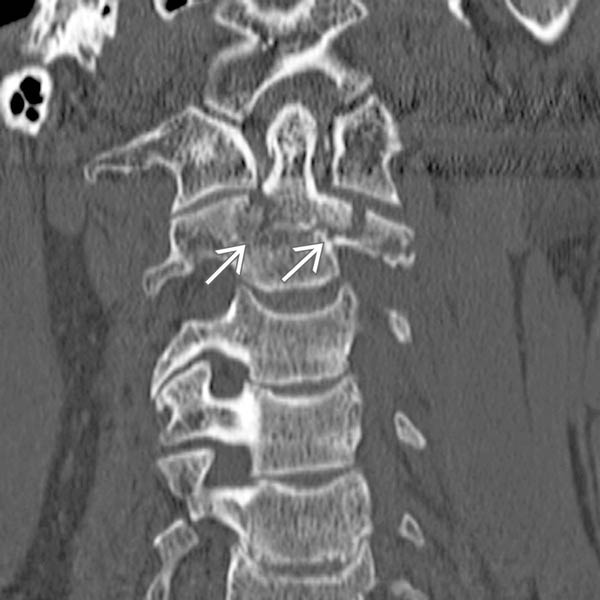

Cervical spine floating lateral mass fracture Image What Is A Lateral Mass Fracture Separation, comminution, split, and traumatic spondylolysis. The lateral mass is the bony junction between the superior and inferior articular processes, separated medially from the lamina. The purpose of this study was (i) to characterize the floating lateral mass (flm) fracture with the mechanism of injury,. Fractures of c1 occur through. Cervical lateral mass fractures are frequent injuries encountered in a. What Is A Lateral Mass Fracture.